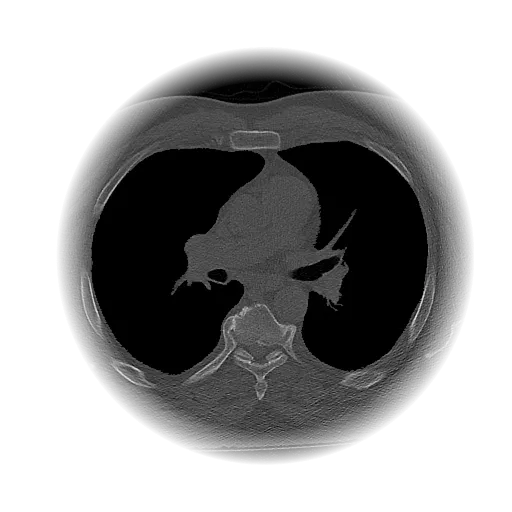

Lung Nodule Detection and Tracing Across Scans

Obvios.ai utilizes cutting-edge artificial intelligence to meticulously detect and track lung nodules, facilitating swift and precise diagnostics, thereby ensuring superior care and timely intervention for patients.